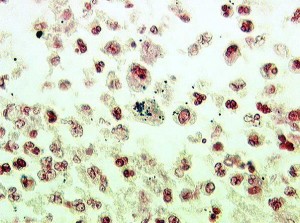

коккобациллы в мазке лечение Оскільки бактерії дуже прості і схожі один на одного, класифікувати їх прийняти за формою клітин. Вироблять вібріони (бактерії у вигляді коми, мають джгутики і постійно рухаються), спіруліни та спірохети (бактерії в форе спіралей), бацили (у формі паличок) і коки (бактерії кулястої форми).

Існують бактерії і проміжних форм, однією з різновидів яких якраз і є коккобацілламі — фора бактерій, яка займає проміжне положення між кулею (коки) і паличкою (бацилою).

Виявляють бактерії зазвичай під мікроскопом, при підозрі на м'який шанкр починають лікувати антибіотиками.